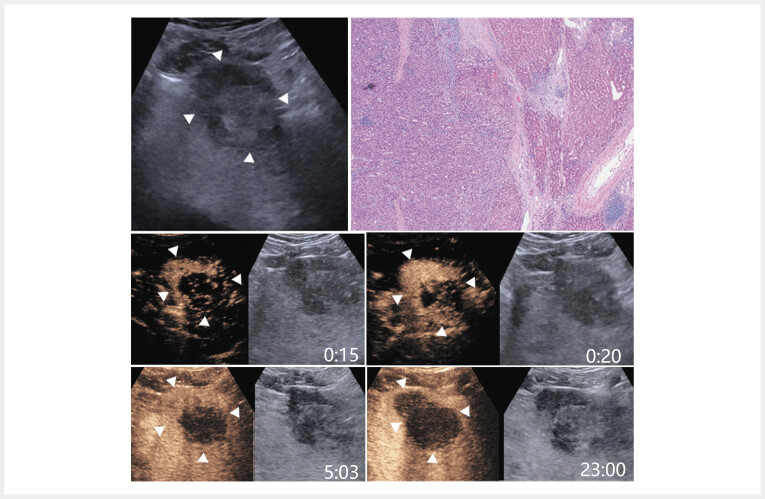

Purpose  This study aimed to compare contrast-enhanced ultrasound (CEUS) features of hepatic angiomyolipoma (HAML) and challenging cases of HCC, mainly those with no hepatitis infection but also with a low level of AFP (non-viral AFP- HCC). Materials and Methods  The study included pathologically confirmed HAMLs and non-viral AFP- HCCs undergoing CEUS from 2012 to 2023. Sonovue (SV) CEUS and Sonazoid (SZ) CEUS characteristics of the two groups were compared. Results  The study included 50 HAMLs (24% on SZ-CEUS) and 88 non-viral AFP- HCCs (21.6% on SZ-CEUS). The CEUS characteristics on SZ-CEUS were similar to those on SV-CEUS to a certain extent. HAMLs more frequently displayed no washout and partial washout with partial no washout, so-called PWNW, in the late phase and post-vascular phase, whereas HCCs more commonly exhibited mild washout. In the post-vascular phase, all non-viral AFP- HCCs exhibited washout, thereby facilitating differentiation from no-washoutHAMLs, superior to SV-CEUS, where some non-viral AFP- HCCs still exhibited no washout in late phase that could not be distinguished from HAMLs. It is noteworthy that PWNW was exclusively found in nodules exhibiting hyper- and hypoechoic separation of the nodules, and hyper- and hypoechoic separation of HAMLs in the post-vascular phase on SZ-CEUS demonstrated PWNW more frequently compared to the late phase, which can potentially help distinguish nodules with hyper- and hypoechoic separation as either HAML or non-viral AFP- HCC. Conclusion: This study highlighted the usefulness of SV- and SZ-CEUS for distinguishing HAML and non-viral AFP- HCC and filled in existing gaps regarding the SZ-CEUS features of HAML.

Abstract Image